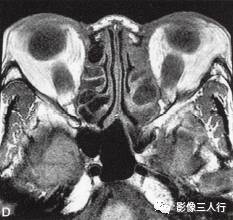

A~C.抑脂T2WI横断面;D~F.T1WI横断面;G~H.T1WI冠状面;I.抑脂T2WI冠状面

横断面显示双侧眼球明显突出,双侧眼球角膜至双侧颧突连线的垂直距离分别为:右侧2.2cm、左侧2.3cm。双侧眼外肌明显增粗,以双侧内、外、上、下直肌明显,短径均可达7mm,且以肌腹增粗明显呈梭形,T1WI等信号(图D~F,图G~H),抑脂T2WI呈明显高信号(图A~C,图I)。双侧眼眶内及球后脂肪增多,双侧眼球内侧至眼眶内侧壁的脂肪厚度增宽。双侧视神经形态及走行正常,双侧眼球晶体、玻璃体形态及信号正常。

影像学检查可帮助该病的诊断与鉴别诊断。CT表现为眼外肌增粗,主要为肌腹增粗,附着于眼球壁上的肌腱不增粗,少数也可同时累及眼外肌肌腹和肌腱。最常累及下直肌,其次为内直肌、上直肌和上提肌,偶尔累及外直肌。MRI表现为受累的眼外肌T1WI低信号,T2WI高信号,压脂T2WI为高信号;晚期眼外肌已纤维化,在T1WI和T2WI均呈低信号。增强扫描急性期时增粗的眼外肌有轻至中度强化,晚期眼外肌纤维化时则无强化。眶内脂肪体积增多表现为球周脂肪尤其是眶前部脂肪的增多。本例影像征象较典型。